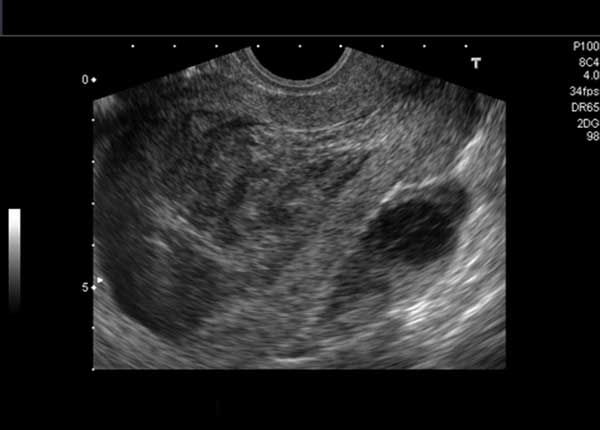

This middle-aged woman has a history of dysmenorrhea. What is your diagnosis based on these images?